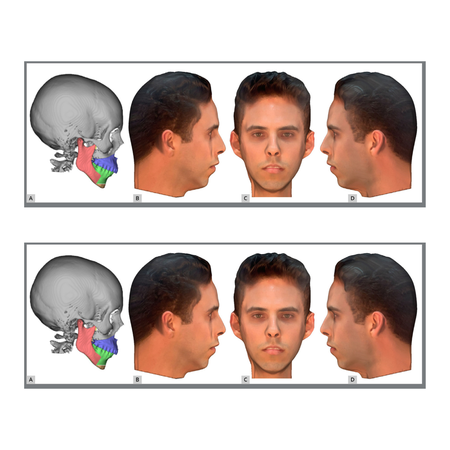

Objetivo: O objetivo deste estudo foi avaliar a percepção da atratividade facial em pacientes com Classe II esquelética e simular possíveis tratamentos para essa condição. Métodos: Foram utilizados escaneamentos dentários, escaneamentos faciais e tomografia computadorizada de feixe cônico (TCFC) de um paciente do sexo masculino. Essas imagens foram agrupadas em um software, onde o arquivo original foi editado para obter um perfil que apresentasse as características esqueléticas e...

Objective: The aim of this study was to assess the perception regarding the attractiveness of the face in patients with skeletal Class II and simulations of possible treatments for this condition. Methods: Dental scans, face scans and cone beam computed tomography (CBCT) of a male patient were used. These images were grouped in a software, where the original file was edited in order to achieve a profile that had the most pronounced skeletal and dental Class II (division 1) features, as well...